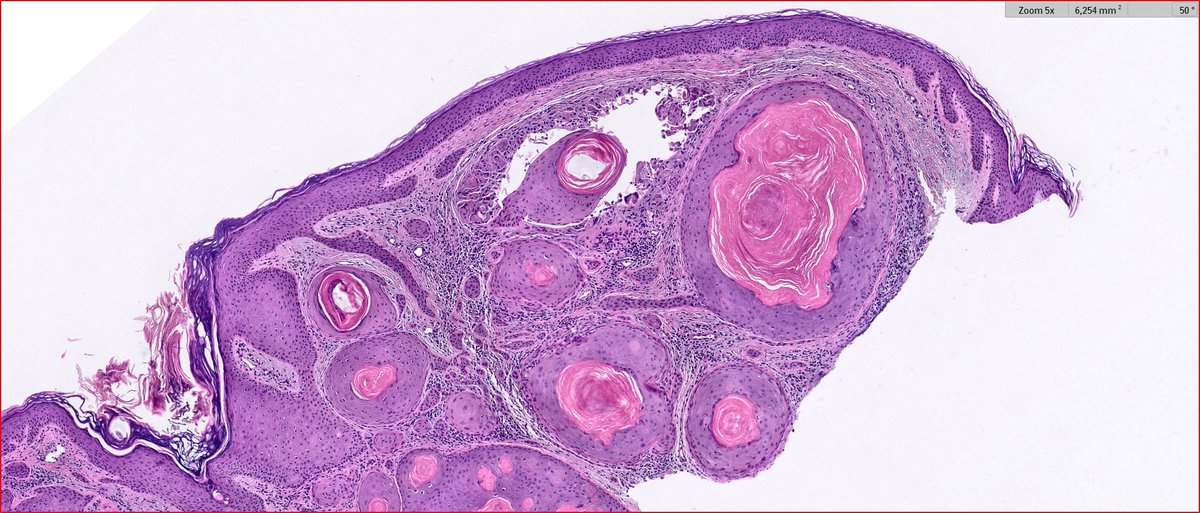

2024 Wk46 ish! RAC9183. M80s Right temple lesion. Previous skin cancers. #TooFarToDiagnose ? #Dermpath